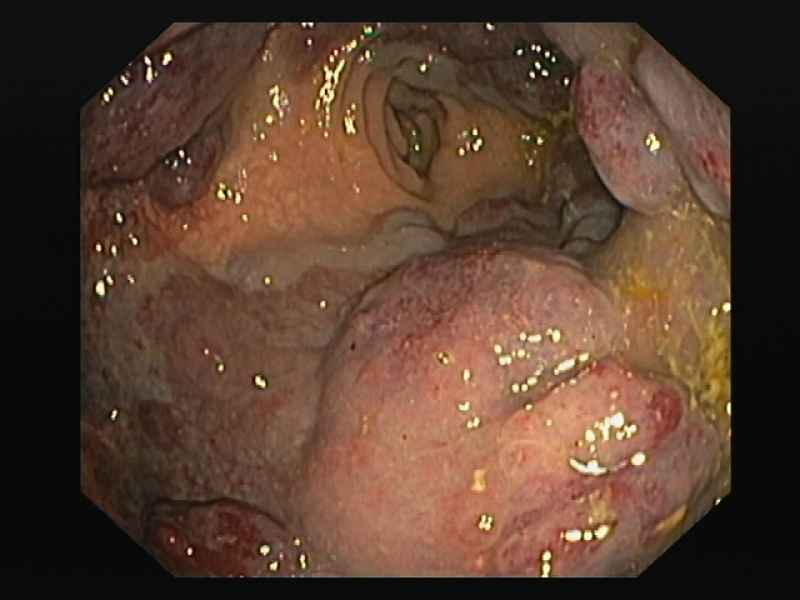

A mantle of rosaries along the colon - 2.º Prémio (Fotografia)

Fotografias